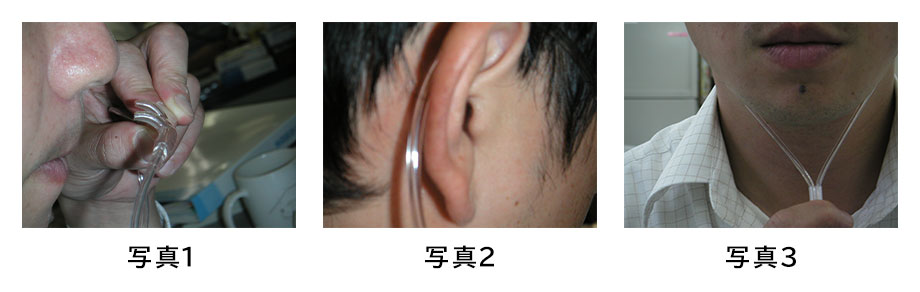

在宅酸素療法で使用する鼻カニューレの装着方法と長時間使用の工夫 - 神戸きしだクリニック 神戸市中央区。

○ カニューラの使い方。

付属パーツの使い方水素吸入器のレンタルはリタエア。

水素吸入器リタエアーの鼻カニューレ カニューラ の上下の向きや装着方法水素吸入器レンタルのリタエア。

在宅酸素療法で使用する鼻カニューレの装着方法と長時間使用の工夫 - 神戸きしだクリニック 神戸市中央区。

在宅酸素療法で使用する鼻カニューレの装着方法と長時間使用の工夫 - 神戸きしだクリニック 神戸市中央区。